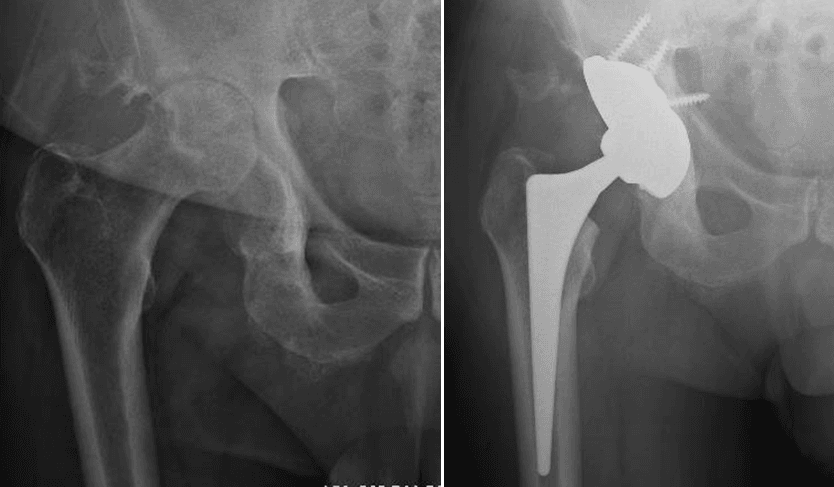

L’intervento di artroprotesi d’anca prevede la sostituzione dell’articolazione dell’anca mediante l’impianto di componenti protesiche in leghe metalliche, come il titanio, accoppiati a materiali plastici (polietilene di ultima generazione) e/o ceramiche. Questo processo include la sostituzione del femore prossimale (testa e collo) e il rivestimento della cavità acetabolare del bacino. L’obiettivo principale di questa procedura è ripristinare un’articolazione stabile e funzionale, migliorando significativamente la capacità di movimento del paziente, alleviando il dolore e migliorando la qualità della vita.

Esistono diverse vie d’accesso chirurgiche per l’artroplastica d’anca; quelle preferite nel nostro centro, a seconda delle caratteristiche del paziente, sono la via postero-laterale e la via anteriore. Ognuna di queste vie ha caratteristiche e vantaggi specifici, e la scelta è sempre basata sulle esigenze individuali del paziente.